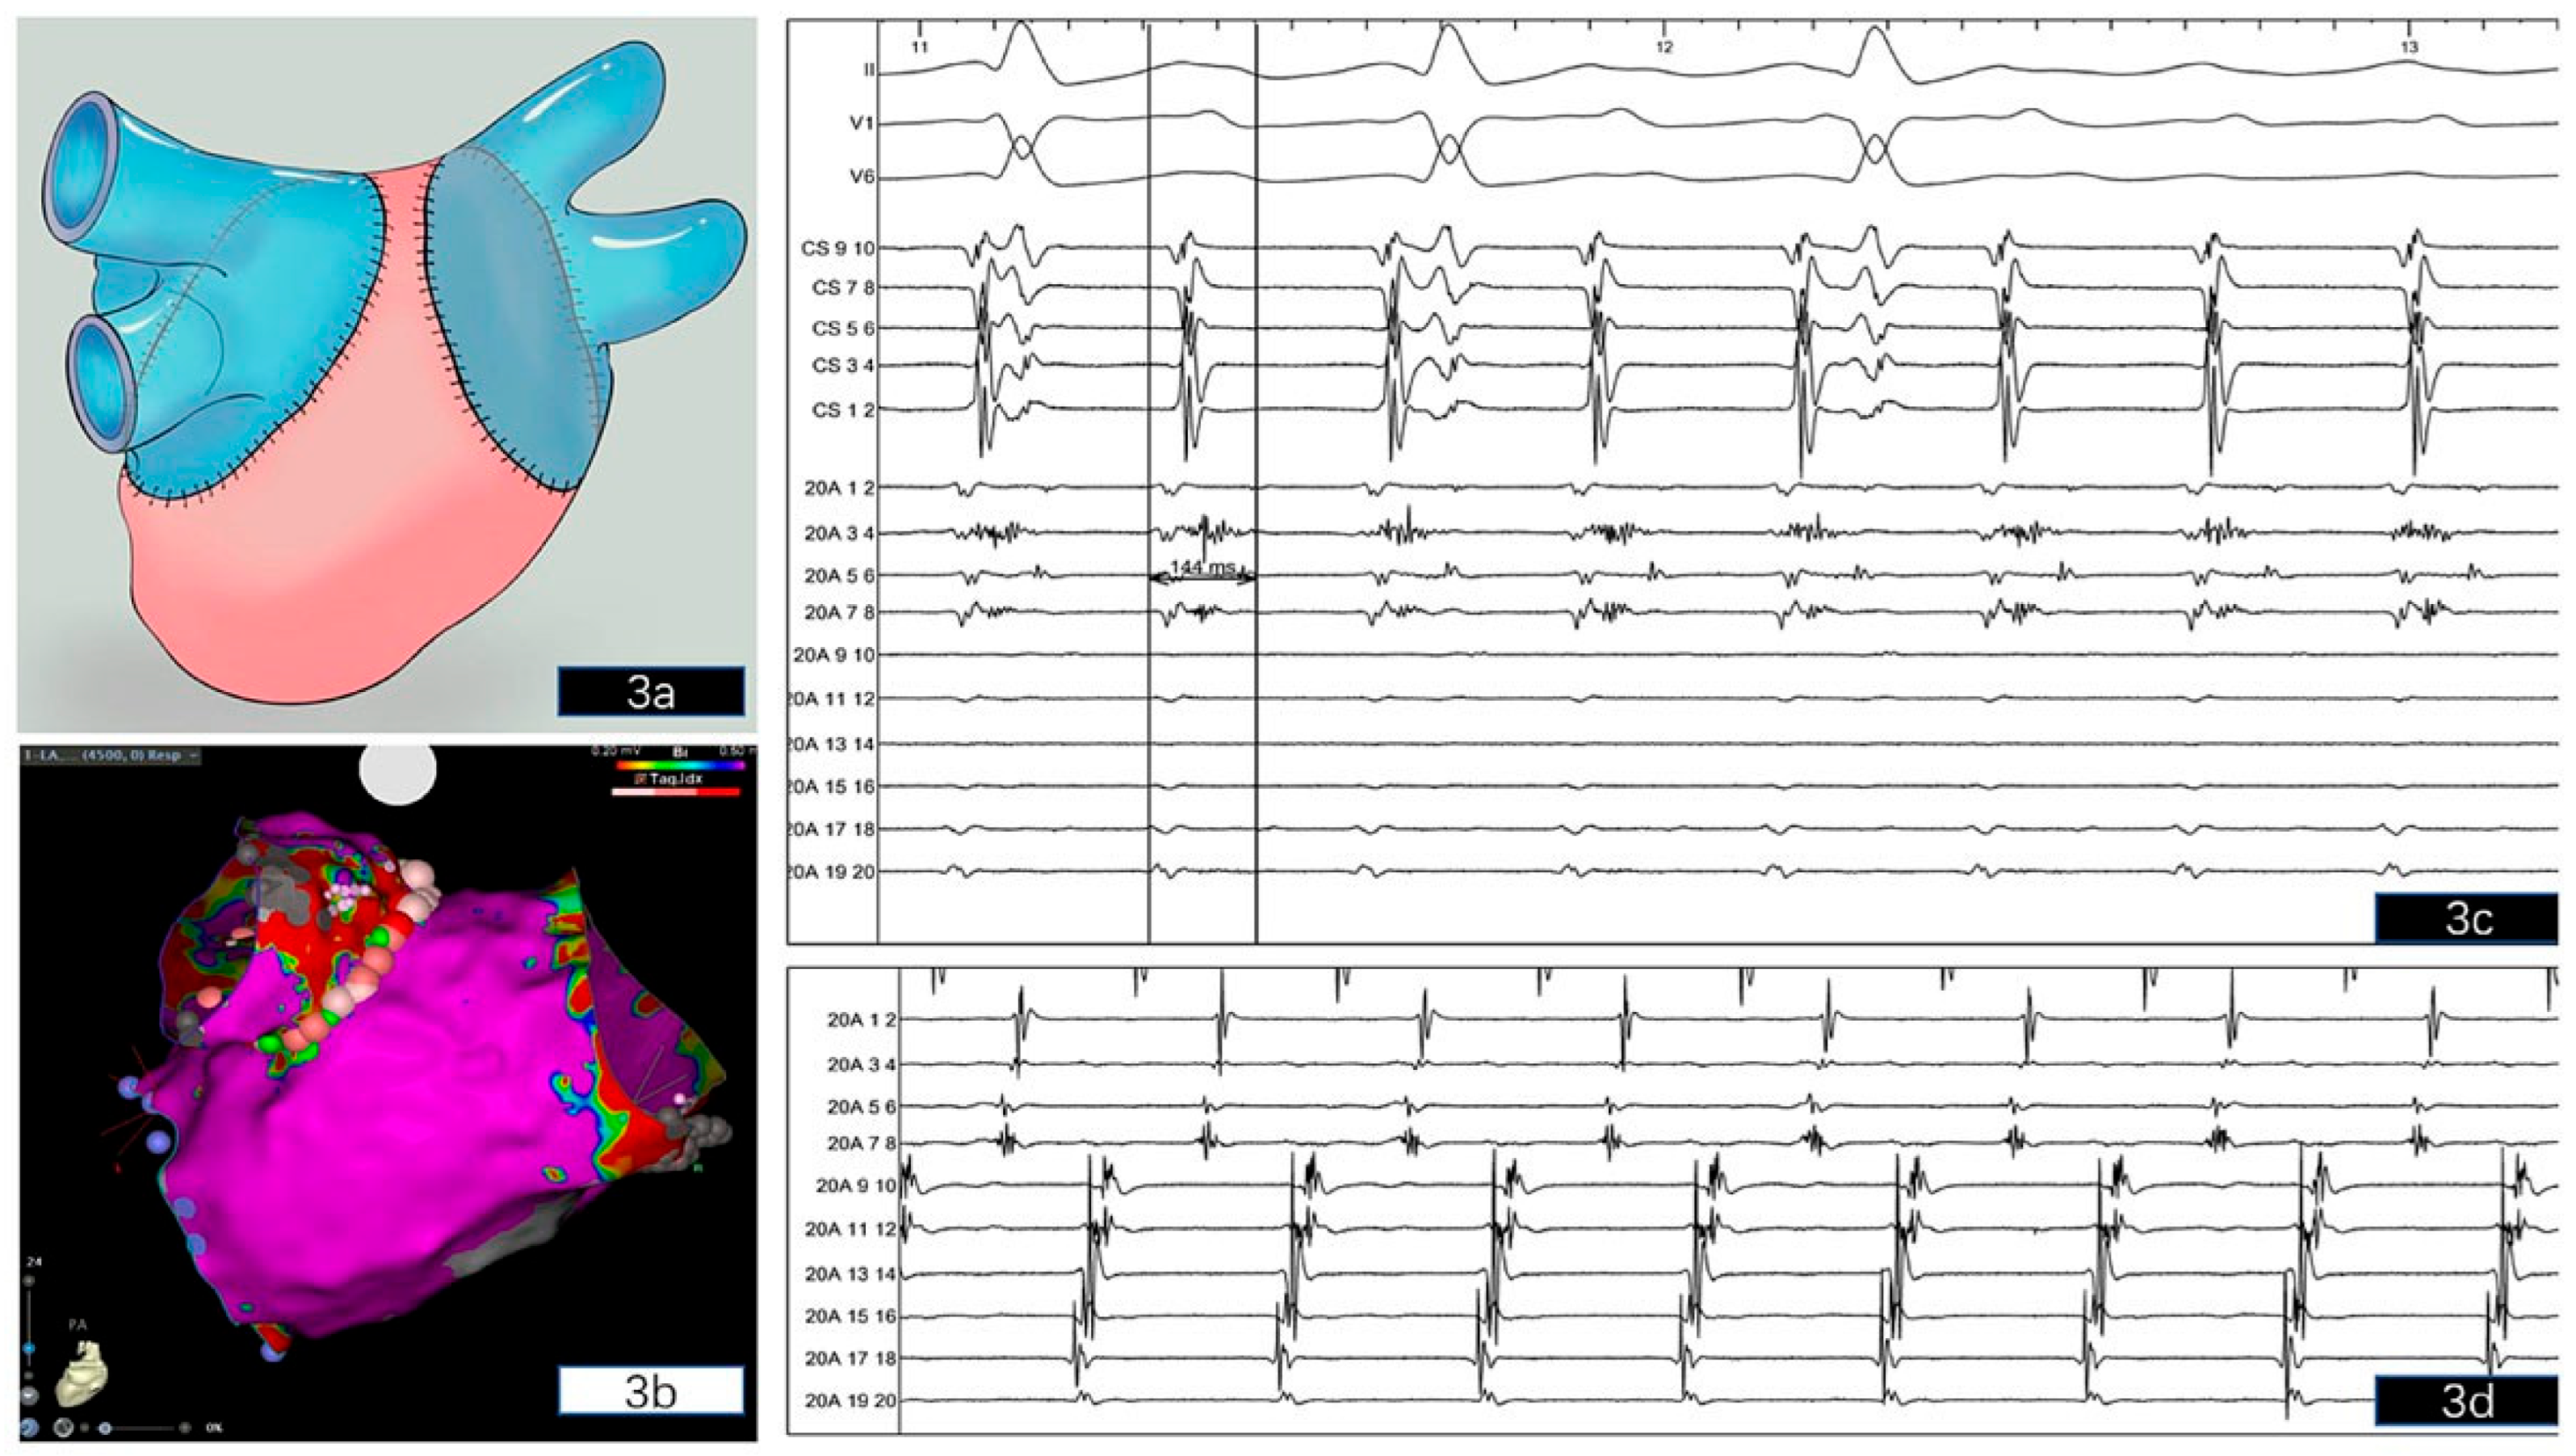

Case description

Electrophysiological study and ablation